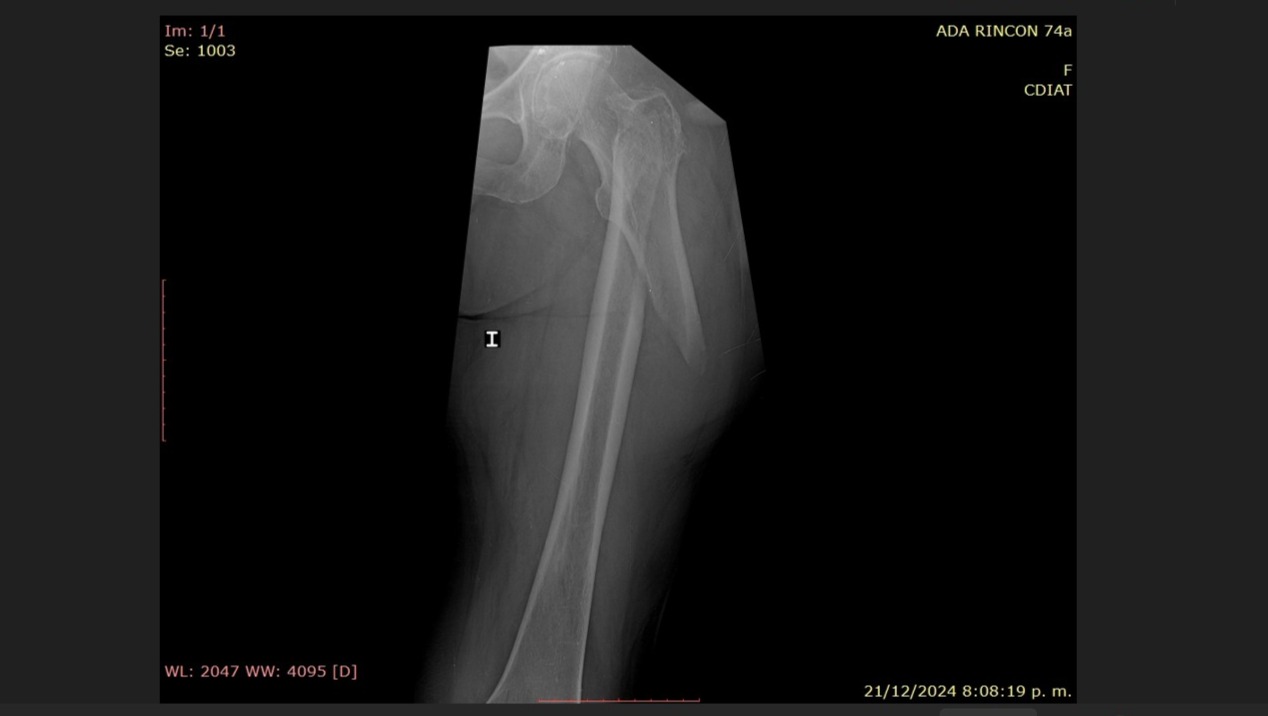

Ese día, mientras cocinaba con el mismo amor con el que siempre ha cuidado de nuestra familia, el hueso de su pierna (fémur) se fracturó de manera inesperada. No fue una caída, sino el impacto silencioso de años enfrentando osteoporosis y sarcopenia, condiciones que han ido debilitando su cuerpo pero nunca su espíritu.

La operación está programada en el Centro Clínico Valentina Canabal CA e incluye la colocación de un Sistema de Clavo Bloqueado para Fracturas Inter y Sub Trocantéricas.